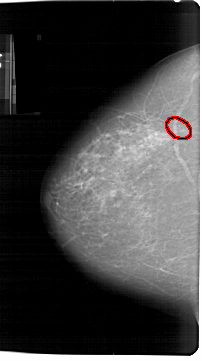

A_1300_1.LEFT_CC

LEFT_CC LINES 6856 PIXELS_PER_LINE 3826 BITS_PER_PIXEL 12 RESOLUTION 43.5 OVERLAY

FILE: A_1300_1.LEFT_CC.OVERLAY

TOTAL_ABNORMALITIES 1

ABNORMALITY 1

LESION_TYPE CALCIFICATION TYPE PUNCTATE-AMORPHOUS DISTRIBUTION CLUSTERED

ASSESSMENT 4

SUBTLETY 4

PATHOLOGY BENIGN

TOTAL_OUTLINES 1